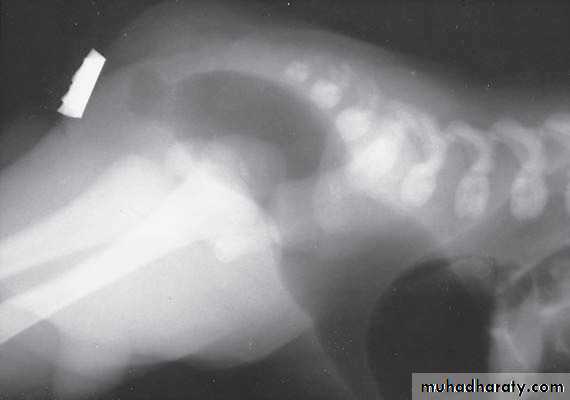

Skeletal anomalies:-

-20% of cases:-1- vertebral.

2-spinal dysraphism.

3-sacral anomalies.

1-x-ray of the spine and chest (sacral , VATER).